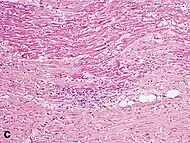

Under the microscope, myocardial infarction presents as a circumscribed area of ischemic, coagulative necrosis (cell death). On gross examination, the infarct is not identifiable within the first 12 hours.[20]

Although earlier changes can be discerned using electron microscopy, one of the earliest changes under a normal microscope are so-called wavy fibers.[21] Subsequently, the myocyte cytoplasm becomes more eosinophilic (pink) and the cells lose their transversal striations, with typical changes and eventually loss of the cell nucleus.[22] The interstitium at the margin of the infarcted area is initially infiltrated with neutrophils, then with lymphocytes and macrophages, who phagocytose ("eat") the myocyte debris. The necrotic area is surrounded and progressively invaded by granulation tissue, which will replace the infarct with a fibrous (collagenous) scar (which are typical steps in wound healing). The interstitial space (the space between cells outside of blood vessels) may be infiltrated with red blood cells.[20]

These features can be recognized in cases where the perfusion was not restored; reperfused infarcts can have other hallmarks, such as contraction band necrosis.[23]